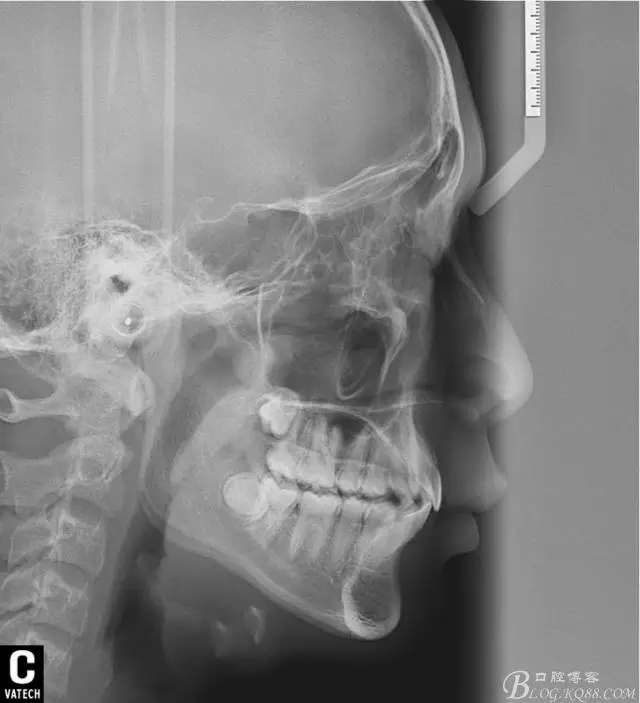

術(shù)后全景,側(cè)位照。

幾何畫板技術(shù)完成術(shù)后頭影測(cè)量!